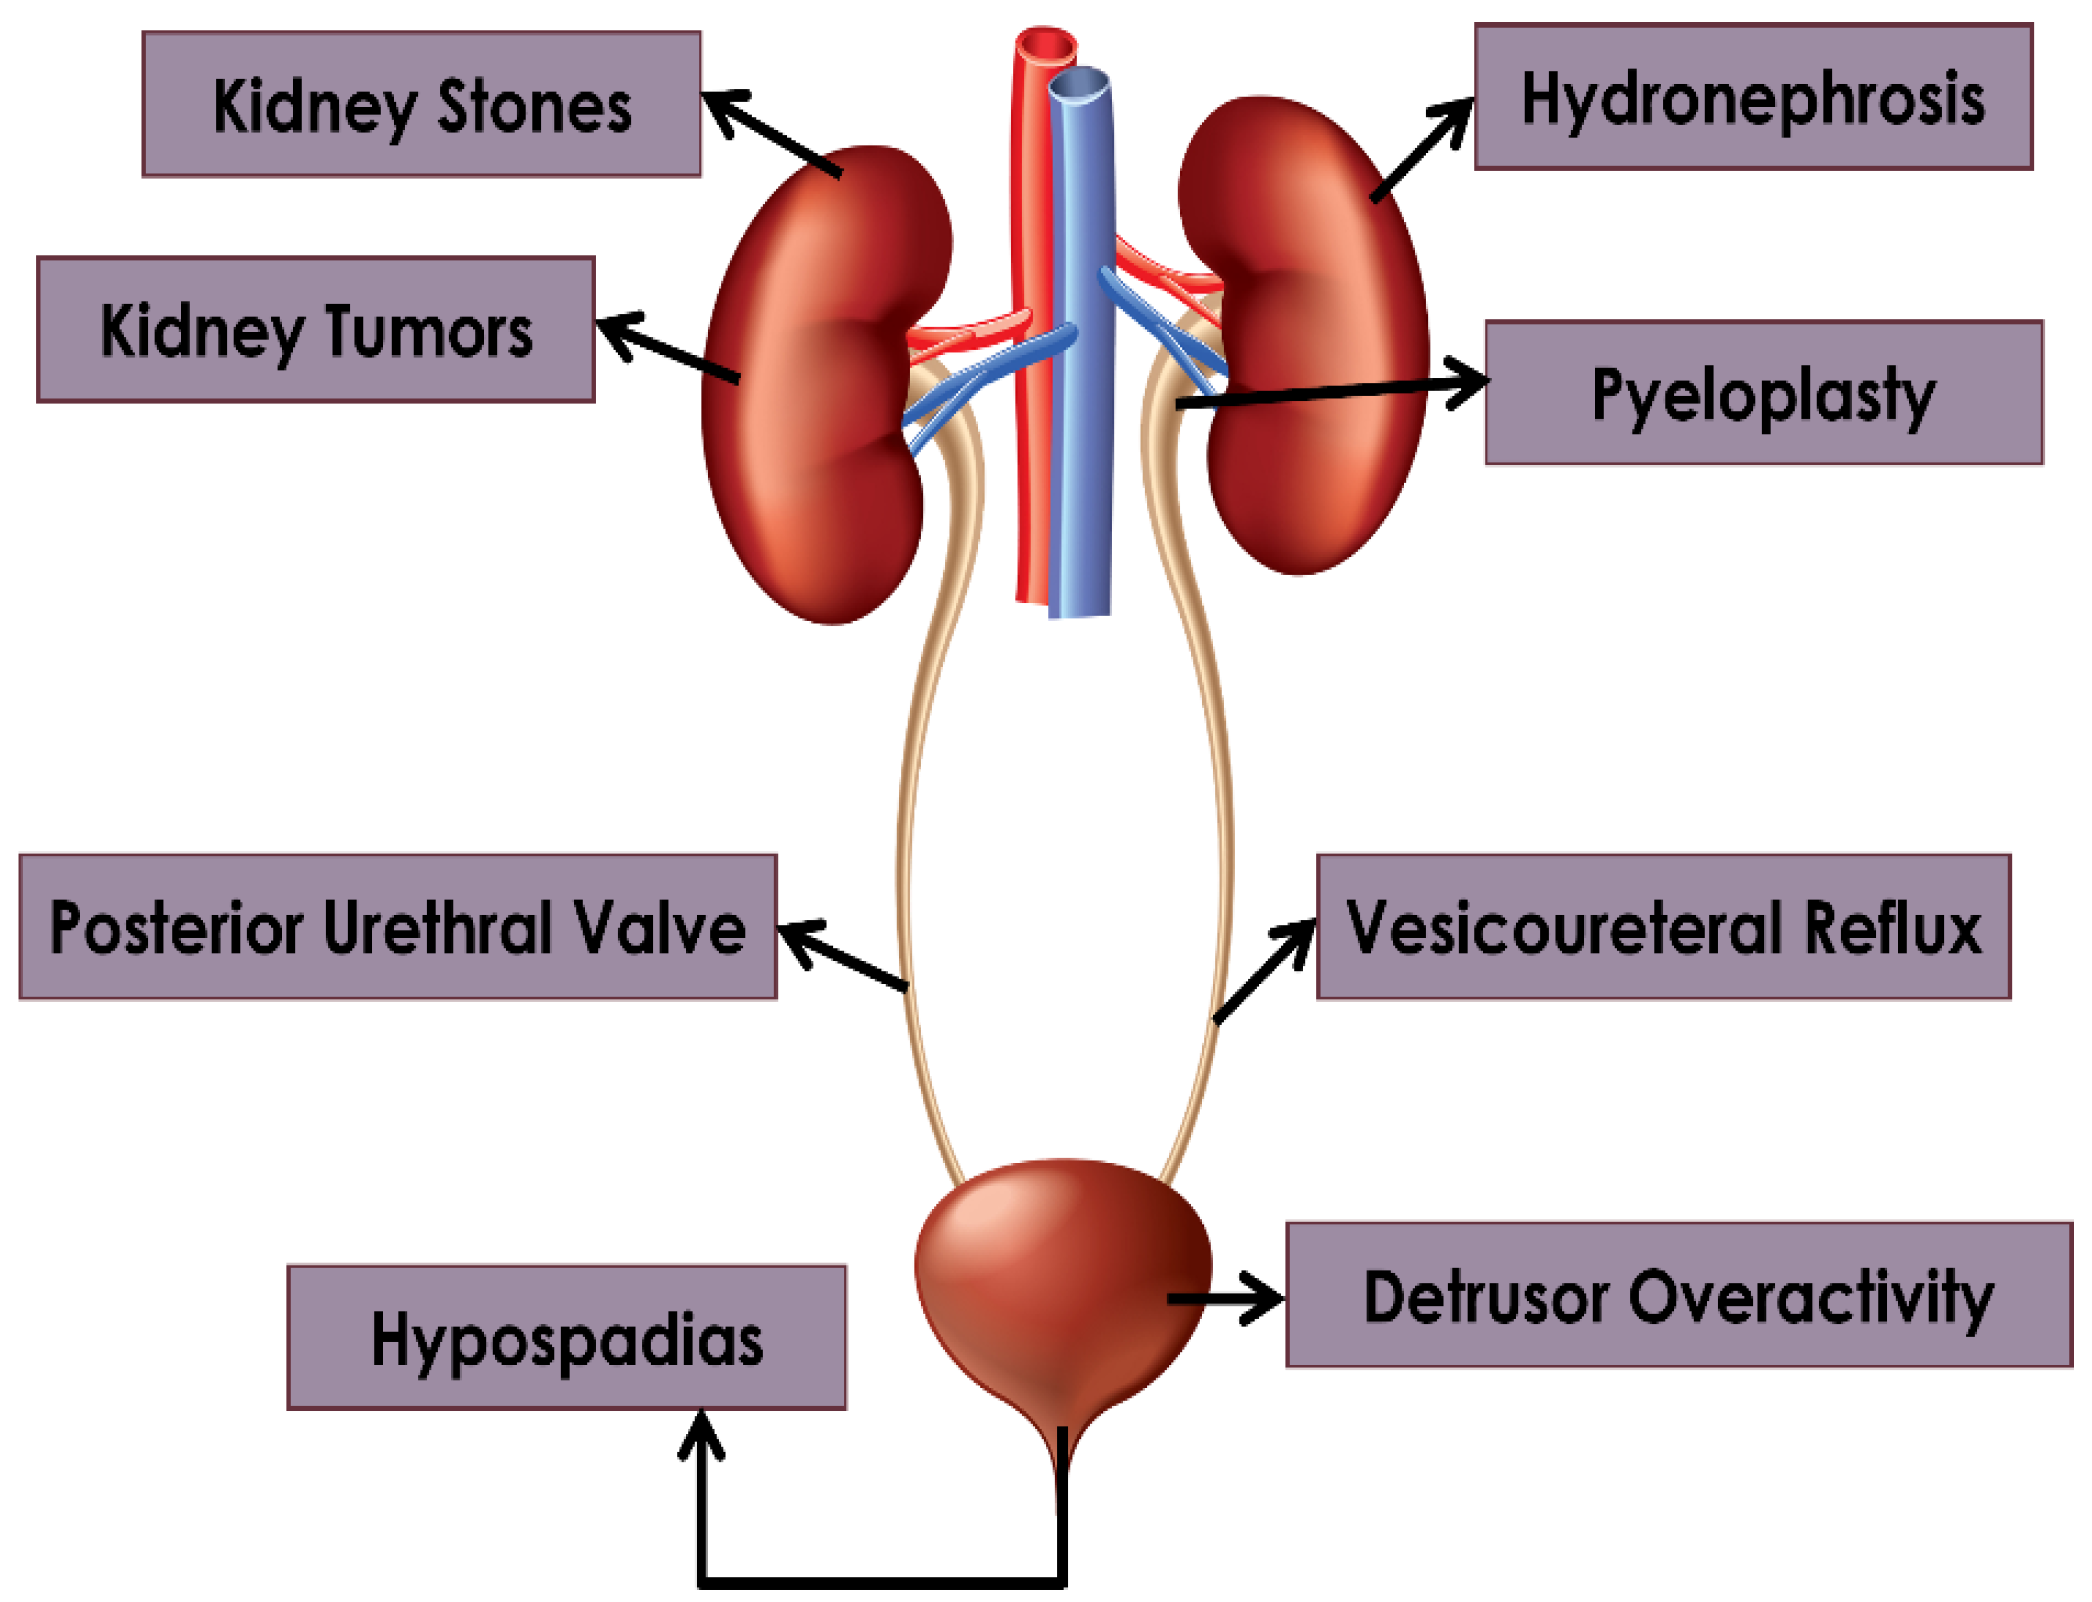

1.1. Background on Pediatric Urology

2. Hydronephrosis

3. Pyeloplasty

4. Pyeloplasty: Kidney Tumors and Stones

5. Vesicoureteral Reflux

6. Detrusor Overactivity

7. Posterior Urethral Valves

8. Hypospadias